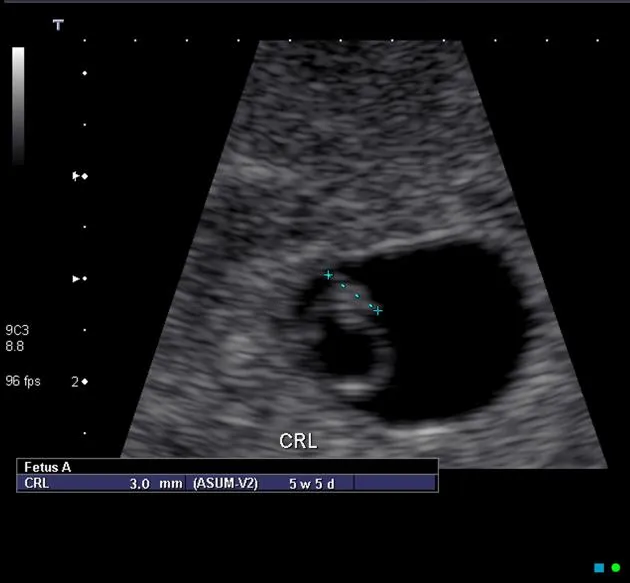

Early USG - Sono Peek-a-Boo

Early ultrasound (USG) is pivotal for confirming pregnancy viability and accurately establishing gestational age (GA). Transvaginal Sonography (TVS) offers earlier and more detailed visualization than Transabdominal Sonography (TAS).

Key TVS Milestones (approximate):

- Gestational Sac (GS): Visible at 4.5-5 weeks. First sign.

- Yolk Sac (YS): Visible at 5-5.5 weeks. Confirms intrauterine pregnancy (IUP).

- Fetal Pole (embryo) with Cardiac Activity: Visible & detectable at 5.5-6 weeks.

- TAS findings are typically observed approximately 1 week later than TVS.

GA Dating Parameters:

- 1st Trimester (Most Accurate):

- Crown-Rump Length (CRL): Most accurate, accuracy ±5-7 days.

⭐ Crown-Rump Length (CRL) is the most accurate biometric parameter for gestational age assessment in the first trimester.

- 1st Trimester (Most Accurate): Crown-Rump Length (CRL). $GA (weeks) \approx CRL (cm) + 6.5$.

- CRL: Most accurate for 1st trimester dating (up to 13+6 weeks).